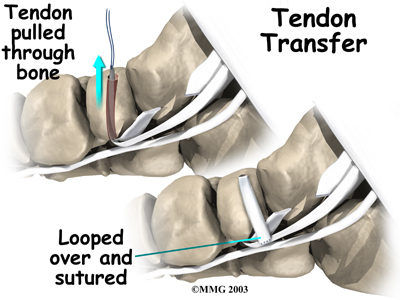

Tendon Graft

A badly degenerated or a ruptured tendon may require a tendon graft. Usually, another tendon in the foot, such as the tendon that flexes the four smaller toes (the flexor digitorum longus), is used as a tendon graft to work in place of the posterior tibial tendon.